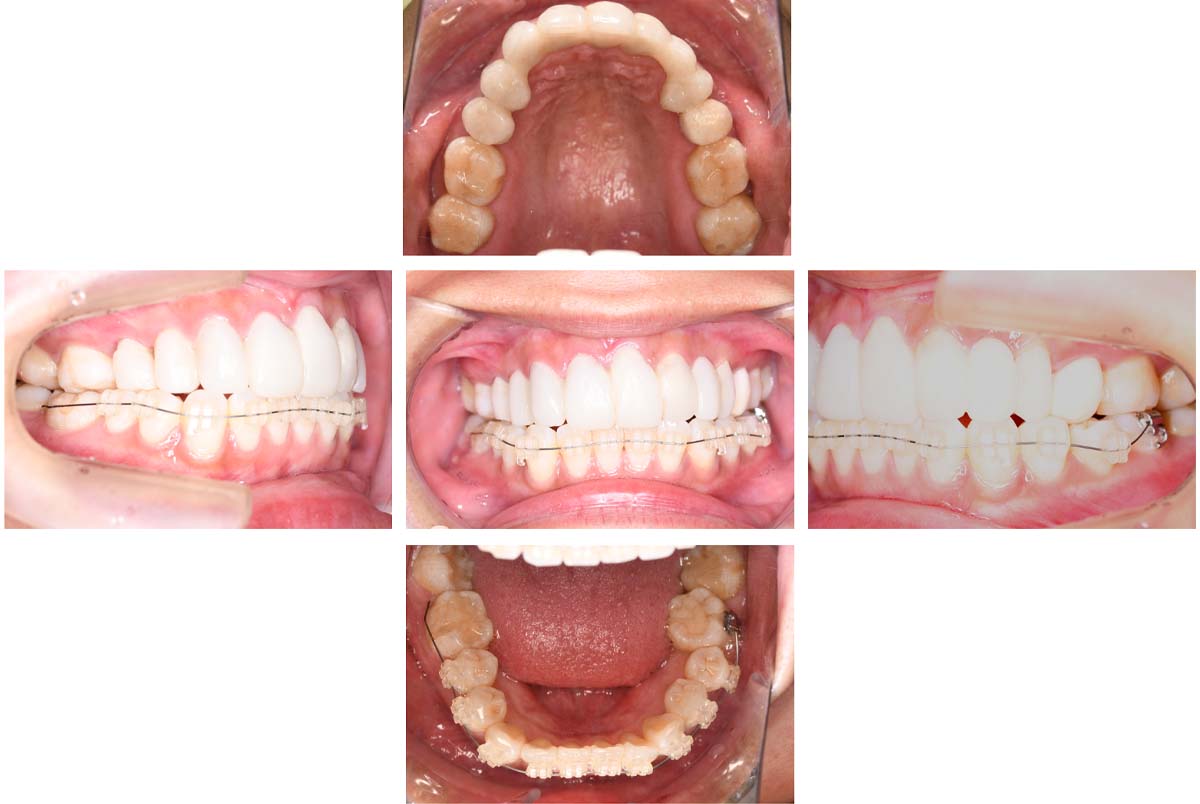

| 治療内容 | ①スプリントを装着 ②副子を装着 ③2024年4月 口腔内反映開始 ④副子を入れた状態の所まで咬合を挙上 (バイトアップ) ⑤2024年5月 上顎前歯部8本に仮歯(TEK) を装着 |

バイトアップ後

![]() |